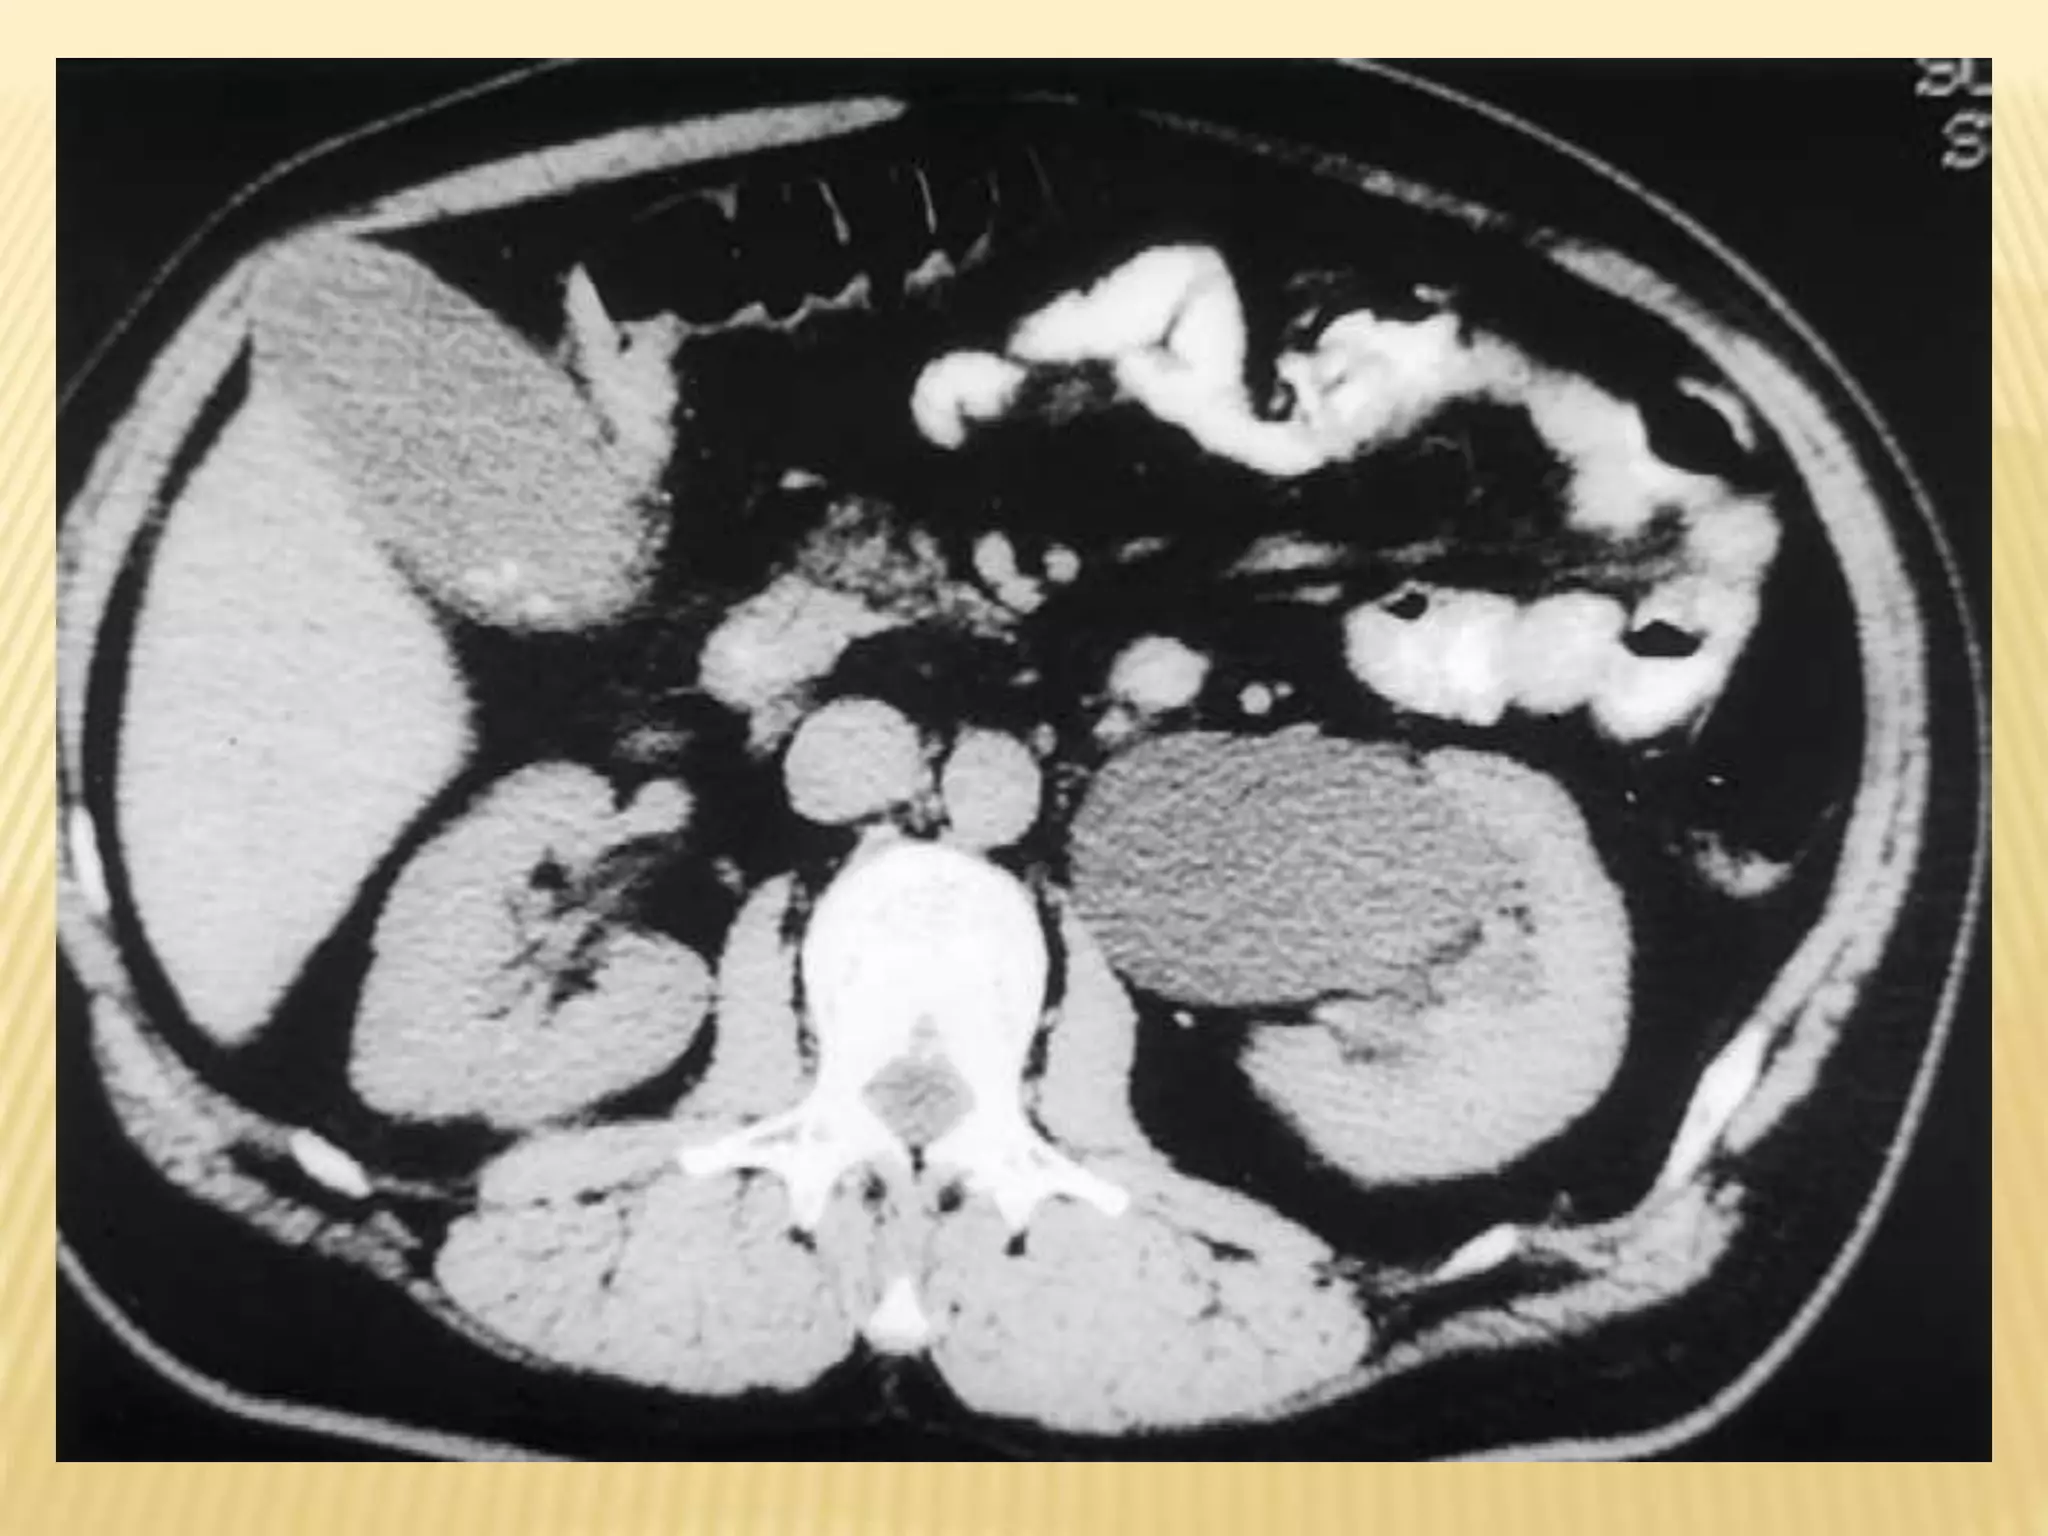

COMPUTED TOMOGRAPHIC SCAN (CT)

- It is an alternative to ultrasonography in the

symptomatic child.

-It is not the preferred modality due to its

radiation exposure.

- In UPJ obstruction, the CT scan typically

shows hydronephrosis without a dilated

ureter.

COMPUTED TOMOGRAPHIC SCAN(CT) - It is an alternative to ultrasonography in the symptomatic child. -It is not the preferred modality due to its radiation exposure. - In UPJ obstruction, the CT scan typically shows hydronephrosis without a dilated ureter.